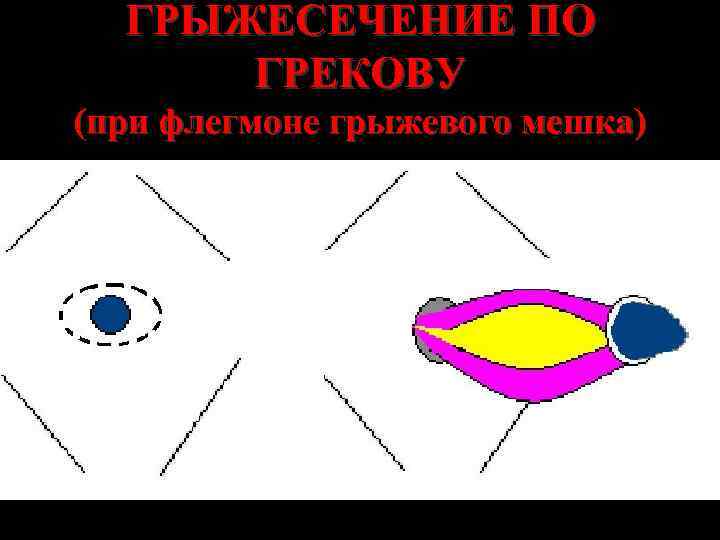

ГРЫЖЕСЕЧЕНИЕ ПО ГРЕКОВУ (при флегмоне грыжевого мешка)